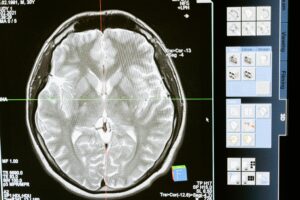

Intricate MRI brain scan displayed on a computer screen for medical analysis and diagnosis.

EVC